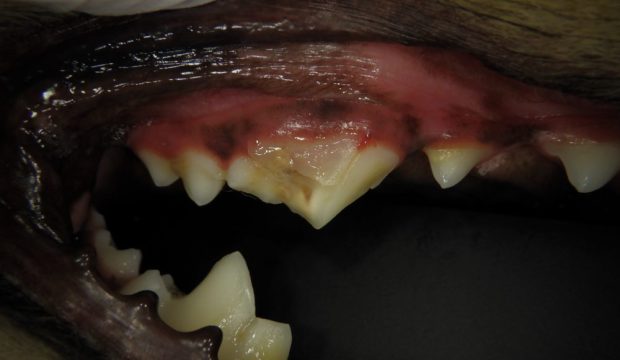

処置直後の歯です。歯茎の裏まで割れていたため歯茎の裏まで処置をしています。

歯茎の状態も以下の通り本来の位置に近い位置までクリーピング(伸びてきている)していて歯周病のリスクも低い状態であるのを確認しました。